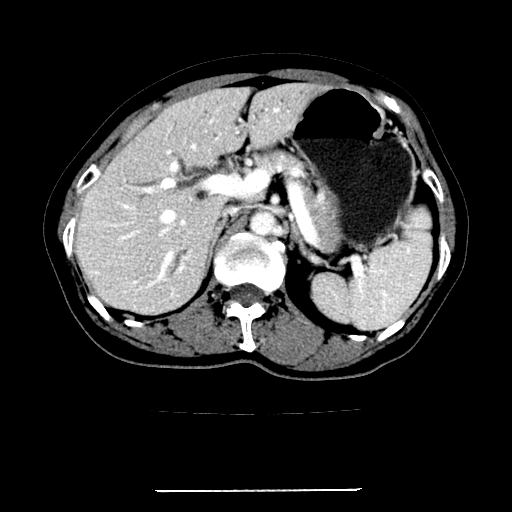

标题: CT22301:女,67岁,上腹部疼痛一周伴皮肤黄染,无发热。 [打印本页]

女,67岁,上腹部疼痛一周伴皮肤黄染,无发热。

左叶肝内胆管结石,并远端肝内胆管扩张。

考虑:肝内胆管结石继发肝内胆管扩张,右肾旋转不良。

肝内外胆管结石并肝内胆管扩张。

肝内外胆管扩张,左叶胆管内结石

1、肝门高密度影下层面和胰头层面可见轻度胆管扩张,而静脉和延迟期均未见扫描完胰头,不能完全排除胰头占位。2、肝门部高密度影,考虑钙化或结石。

考虑肝门胆管癌伴门脉左支受侵包埋,建议mrcp进一步检查。